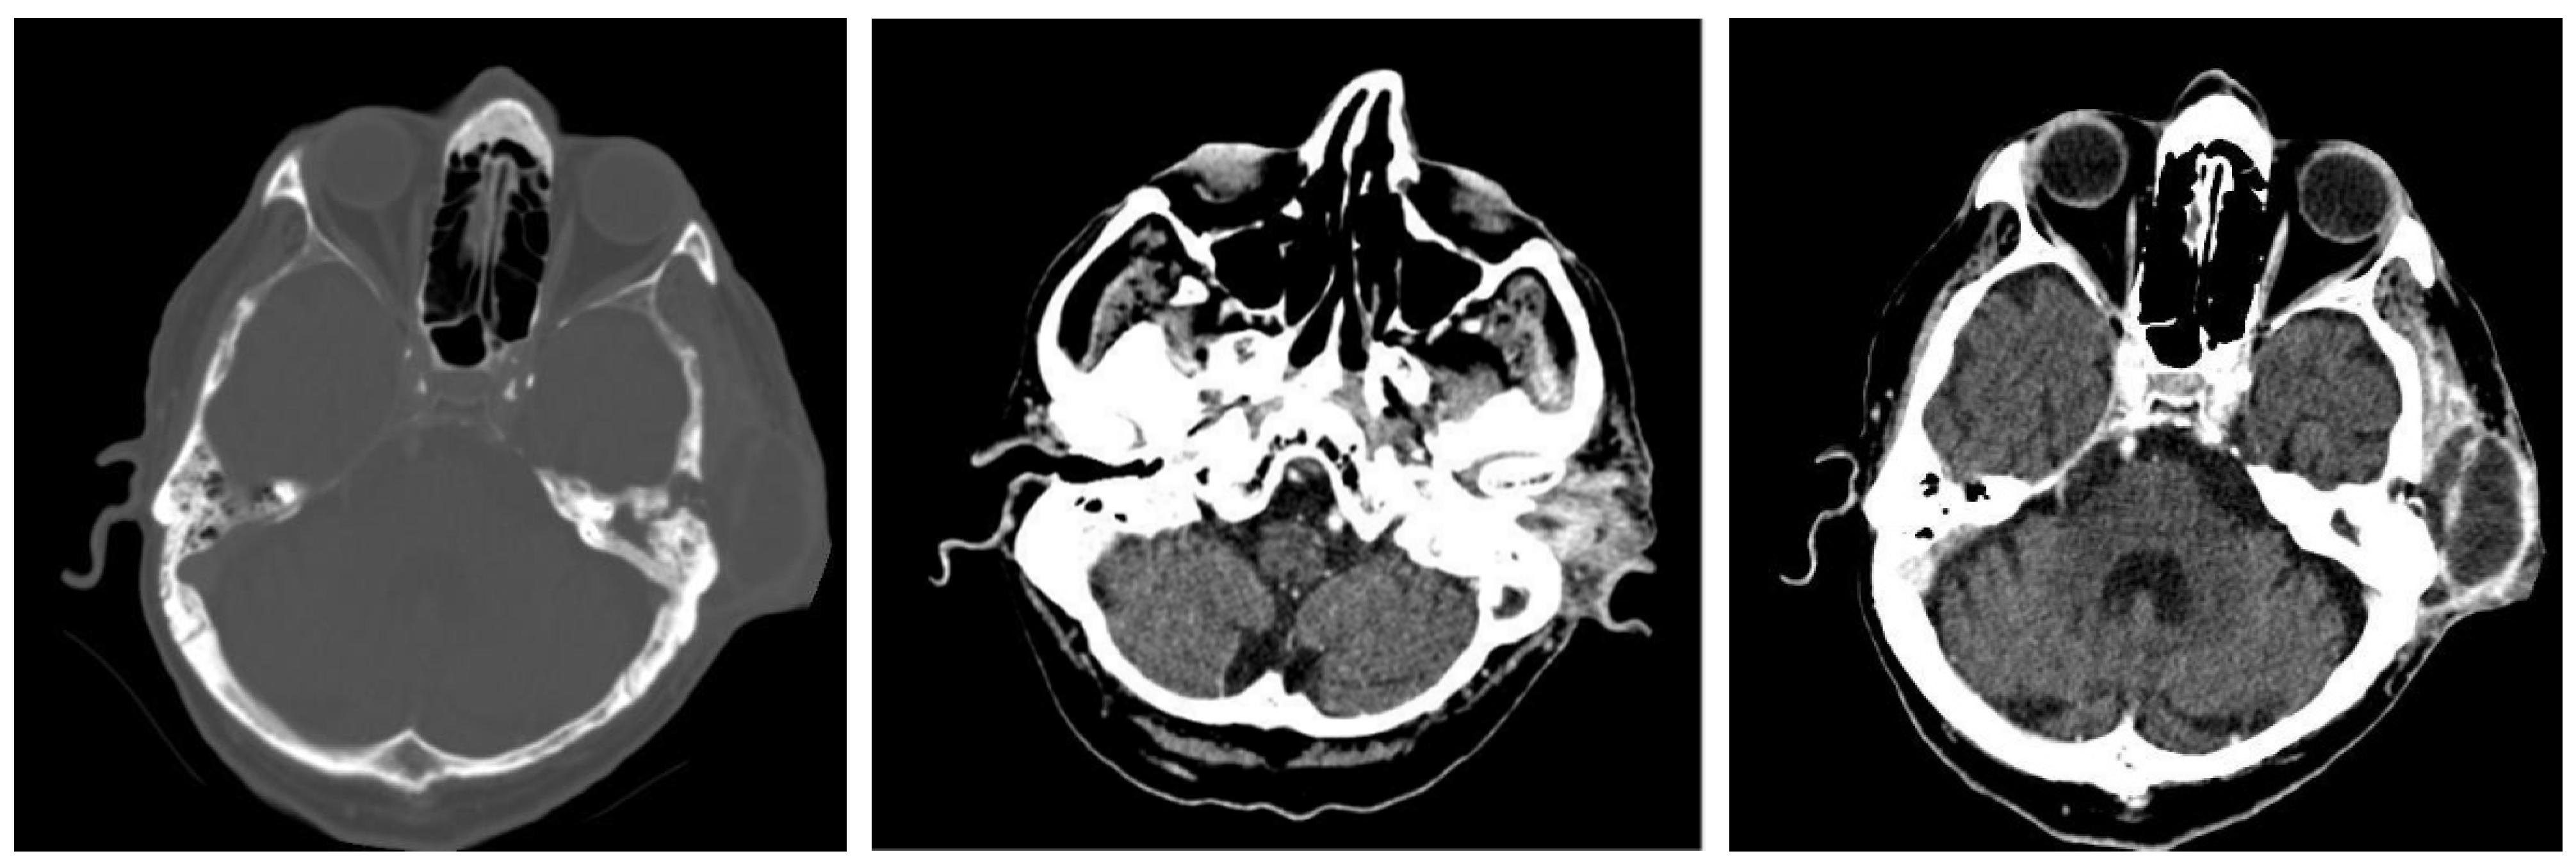

3.1.2. Computed Tomography and Magnetic Resonance Imaging

| CT Aspects | Number of Patients | Percentage |

|---|---|---|

| Fluid accumulation | 168 | 100% |

| Osteolysis | 152 | 90.47% |

| Osteocondensations | 128 | 76.19% |

| Cholesteatoma | 48 | 28.57% |

| Exocranial extensions | 48 | 28.57% |

| Intracranial extensions | 24 | 14.28% |

| Changes to the external auditory canal | 68 | 40.47% |

| Ossicular chain damage | 144 | 85.71% |